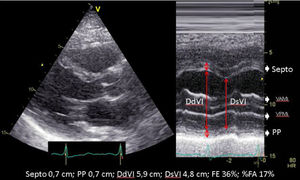

El parámetro ecocardiográfico más utilizado en la práctica clínica es la fracción de eyección del VI (FEVI), a pesar de que, en ocasiones, no refleja adecuadamente la función ventricular, precisando completar el estudio con el análisis de los diámetros, los volúmenes, la geometría, la masa y el grosor parietal, la contractilidad segmentaria, el estudio de función diastólica y la estimación de presiones de llenado, aspectos que se alejan del objetivo contemplado en este capítulo (tabla 1)6-10. En cuanto a la valoración de la función del VD, revisado en otro capítulo de esta serie, la excursión sistólica del plano del anillo tricuspídeo (TAPSE) y la velocidad máxima de la onda sistólica (onda St’)7,11,12 son los parámetros más utilizados por su fácil estimación y su escasa variabilidad interindividual. Asimismo, es un parámetro que depende de la precarga y la poscarga13, y no debe utilizarse en caso de implante de anillo o prótesis a nivel tricuspídeo o calcificación anular severa.

| A.2. Fracción de acortamiento (FA) | ||

| Se trata de un parámetro subrogado de la FE (Teichholz) en la que se valora los DtTDVI y DtTSVI. Presenta las mismas limitaciones que las comentadas en la estimación de la FEVI por Teichholz. | ||

| A.3. Diámetro telesistólico del ventrículo izquierdo (DtSVI) | ||

| La valoración del DtSVI es un parámetro que nos puede alertar de una posible disfunción ventricular a pesar de presentar una FE normal por un aumento de precarga, como es el caso de la regurgitación aórtica y mitral. | ||